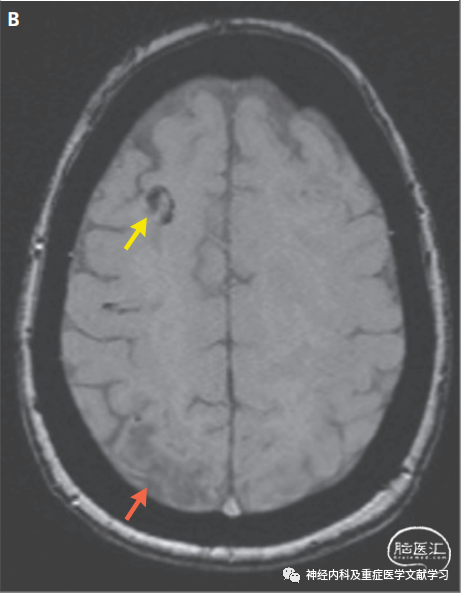

图3 累及多脑叶PRES患者的影像学改变。

一名因慢性淋巴细胞淋巴瘤接受免疫抑制治疗58岁男性,主因嗜睡和癫痫发作入院。图A患者颅脑MRI FLAIR轴向图像显示右侧额叶有细微的脑白质信号改变(箭头)。B图2天后的MRI扫描显示累及枕叶和顶叶内侧区域的新发FLAIR高信号(箭头)。